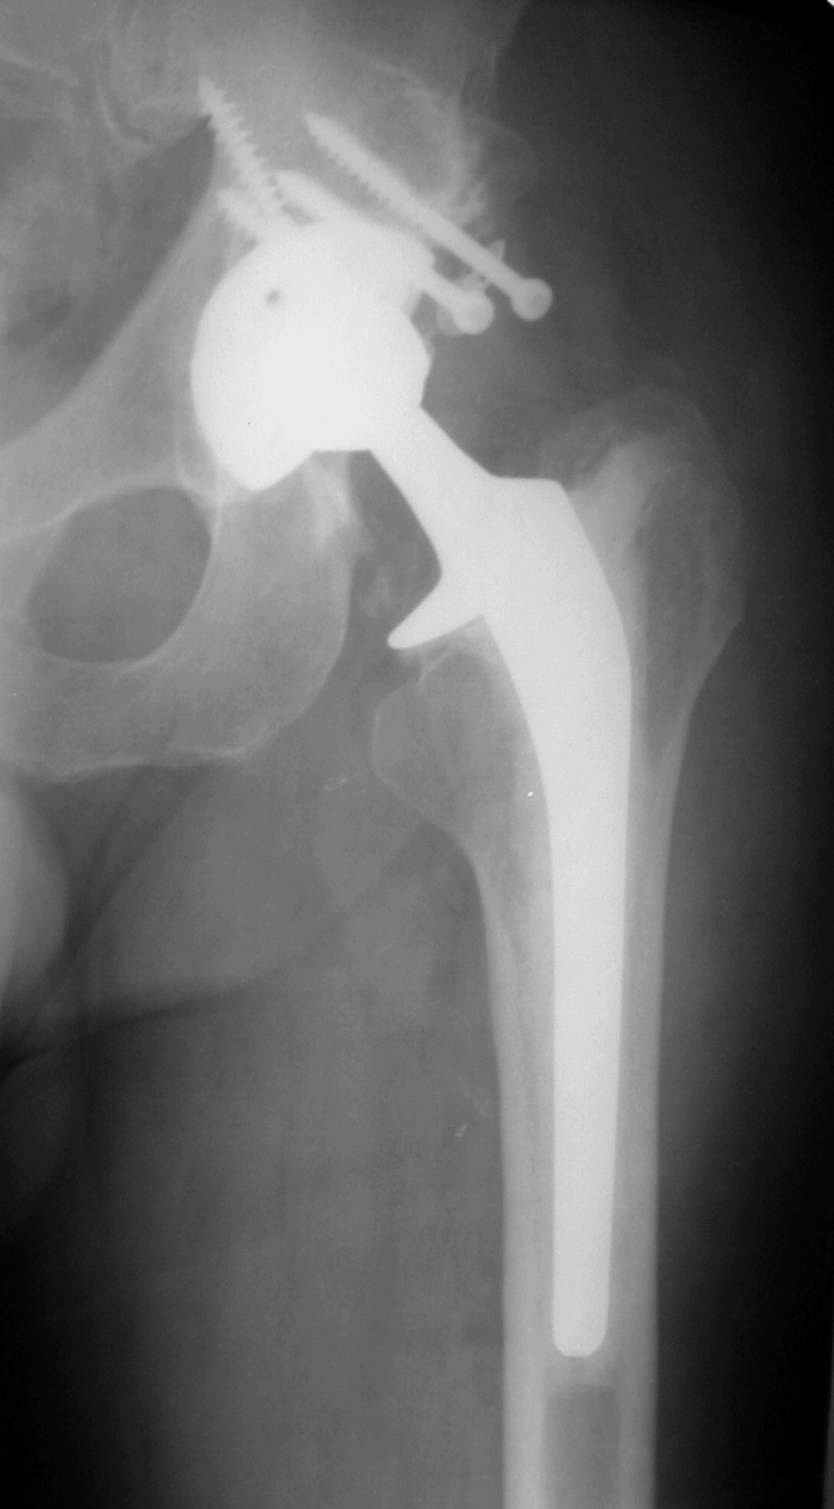

РАВ> Есть ли у Вас примеры установки протеза при обширных дефектах впадины?

РАВ> Какой был самый большой дефицит задней колонны, какой срок наблюдения,

РАВ> довольны ли Вы результатом?

Максимальные сроки наблюдения 5-6 лет. С появлением современных эндопротезов результаты сравнимы с первичным протезированием при обычном КА. Но, каждая операция нестандартная и требуется

тщательнейшее планирование каждого шага и необходимо иметь несколько запасных вариантов.

Схематично можно сказать так - если есть контакт с 60% и более ВВ, то этого достаточно для последующей биологической фиксации чашки. Опять же НО, мы стараемся "подрыться" фрезами так, что бы был приемлимый упор чашки, а фиксация аутотрансплантата головки была прочной без каких либо дефектов и зазоров.

Если у Вас есть дефект крыши, то никакая пластика не выдержит, лучше сразу ставить опорные кольца, все зависит от локализации костного дефекта.

В институте совместно с фирмой Зиммер достаточно регулярно (практически ежемесячно) проводятся 2-х недельные циклы по различным вопросам эндопротезирования. Если есть возможность и желание, мы готовы поделиться с Вами нашим опытом, тем более есть что показать и что обсудить - в настоящее время ежедневно выполняется от 6 до 10 эндопротезирований коленного и тазобедренного сустава. В качестве примеров хочу показать 2 наблюдения, через 1 год и 5 лет после операции

5 лет